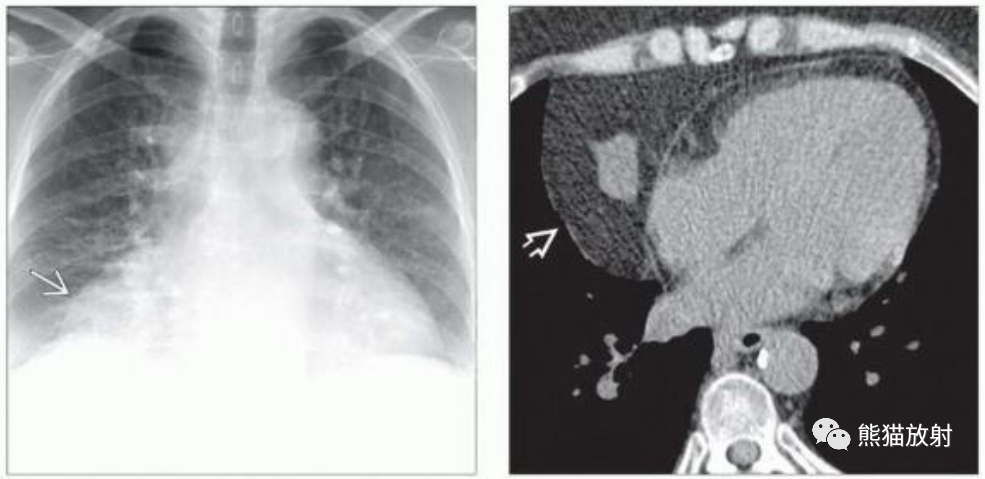

(左)50岁女性,胸腺脂肪瘤,无症状。PA胸片显示位于右侧心膈角肿块。

(右)同一患者的轴位NECT显示大量脂肪密度为主,中央见软组织密度结节。胸腺脂肪瘤经常累及前纵隔的下部。